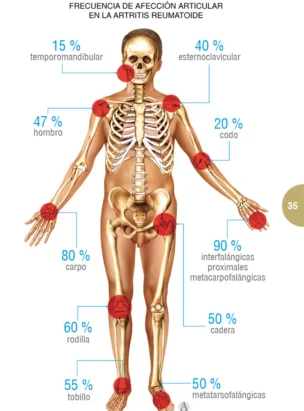

Artritis Reumatoide